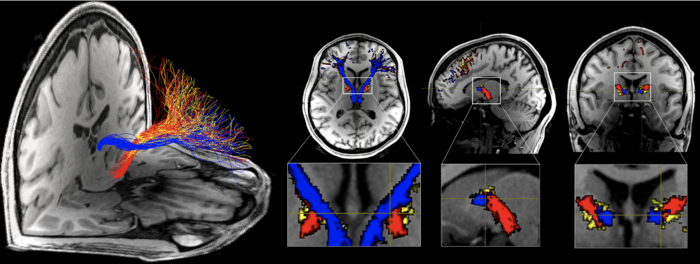

IMAGE: STRUCTURAL CONNECTIONS WITH THE PREFRONTAL CORTEX MODELED FROM TARGETED NUCLEI IN THE SUBCORTEX (BLUE: HABENULA, YELLOW: ANTERIOR THALAMUS, RED: VENTRAL TEGMENTAL AREA) USING DIFFUSION MRI TRACTOGRAPHY. MICROSTRUCTURAL PROPERTIES OF THE HABENULA TRACT WERE UNIQUELY REDUCED IN INDIVIDUALS WITH COCAINE OR HEROIN USE DISORDER. RESULTS HIGHLIGHT THE POTENTIAL SPECIFICITY OF DISTINCT PREFRONTAL CORTICAL CONNECTIONS TO THE NEUROPATHOLOGY OF DRUG ADDICTION view more

For the first time in the human brain, a team led by Rita Z. Goldstein, PhD, and Junqian Xu, PhD, used diffusion magnetic resonance imaging (MRI) tractography to investigate the microstructural features of the PFC-habenula circuit in people with cocaine or heroin addiction compared to healthy control participants. Diffusion MRI tractography uses noninvasive brain imaging to model fiber bundles in the living human brain.

“In addition to identifying microstructural differences, specifically reduced coherence in the orientation of the white matter fibers in the cocaine-addicted group that comprised both current cocaine users and those with short-term abstinence, we extended results beyond cocaine (a stimulant) to heroin (an opioid), suggesting that abnormalities in this path may be generalized in addiction,” said Sarah King, a PhD student in Neuroscience in the Graduate School of Biomedical Sciences at Icahn Mount Sinai, who led the analyses and is first author of the paper. “Importantly, we found that across all addicted individuals, greater impairment was correlated with earlier age of first drug use, which points to a potential role for this circuit in developmental or premorbid risk factors.”